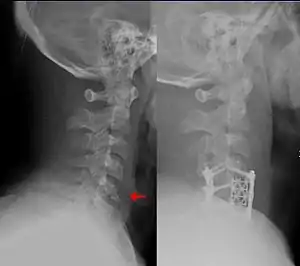

| Teardrop fracture of the cervical spine before and after treatment with metal fixation | |

A flexion teardrop fracture is a fracture of the anteroinferior aspect of a cervical vertebral body due to flexion of the spine along with vertical axial compression.[1] The fracture continues sagittally through the vertebral body, and is associated with deformity of the body and subluxation or dislocation of the facet joints at the injured level.A flexion teardrop fracture is usually associated with a spinal cord injury, often a result of displacement of the posterior portion of the vertebral body into the spinal canal.[2]

The flexion teardrop fracture should not be confused with a similar-looking vertebral fracture called "extension teardrop fracture". Both usually occur in the cervical spine, but as their names suggest, they result from different mechanisms (flexion-compression vs. hyperextension). Both are associated with a small fragment being broken apart from the anteroinferior corner of the affected vertebra. Flexion teardrop fractures usually involve instability in all elements of the spine at the injured level, commonly occur at the C4-C7 vertebra, and have a high association with spinal cord injury (in particular anterior cord syndrome). In comparison, the extension-type fracture occurs more commonly at C2 or C3, causes less if any disruption to the middle and posterior elements, and does not usually result in spinal cord injury (however it may co-occur with more dangerous spine injuries).